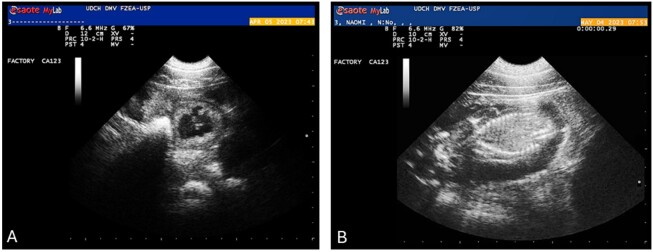

Abstract Image